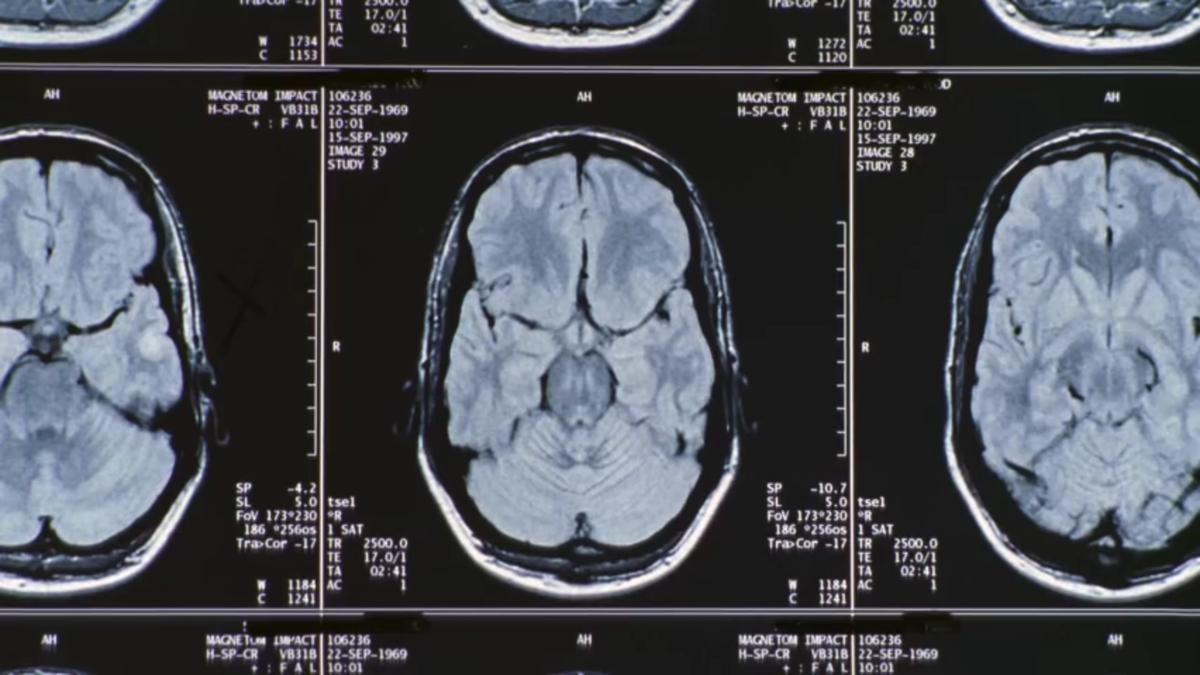

МРТ головного мозга – «изгиб» мозолистого тела.

Интересный факт: на срезах МРТ головного мозга, показанных в данном эпизоде, мозолистого тела не видно :)

А вот так мозолистое тело выглядит на МРТ в Т1-режиме в сагиттальной проекции ()